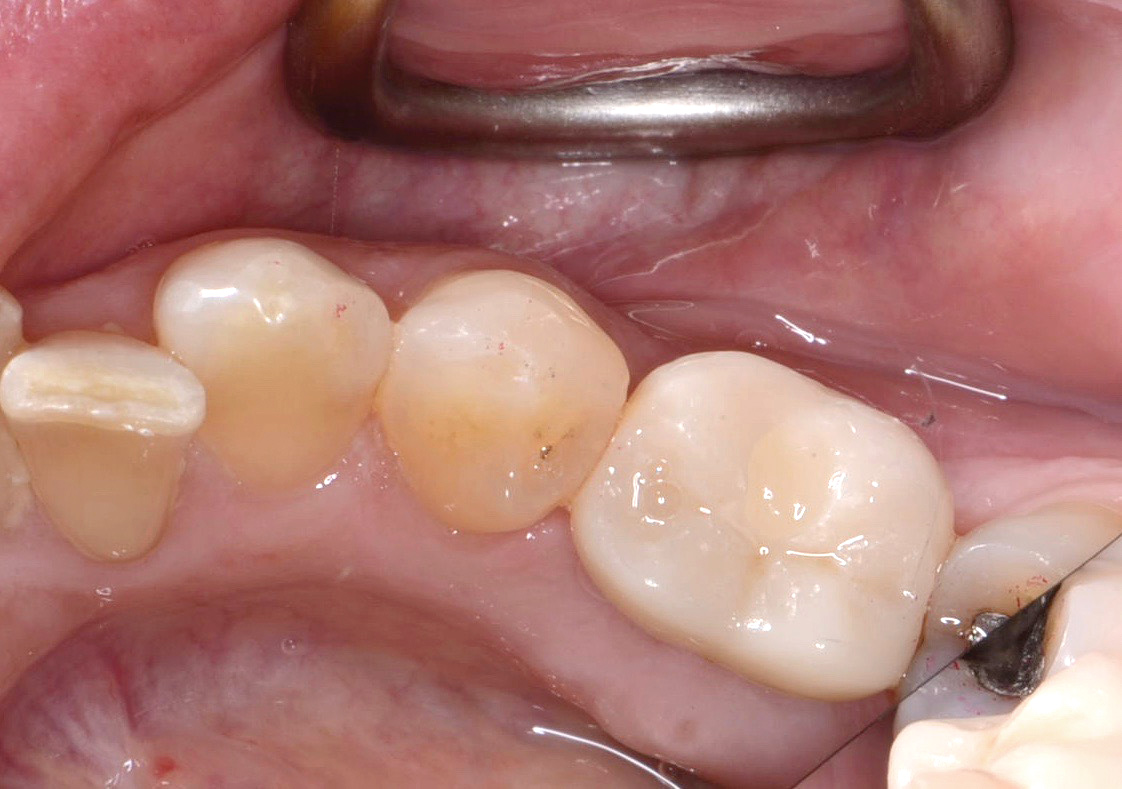

Fig 8. Loss of restoration and subsequent tissue overgrowth from broken abutment screw as shown in the radiograph (Fig 9).

Figure 8